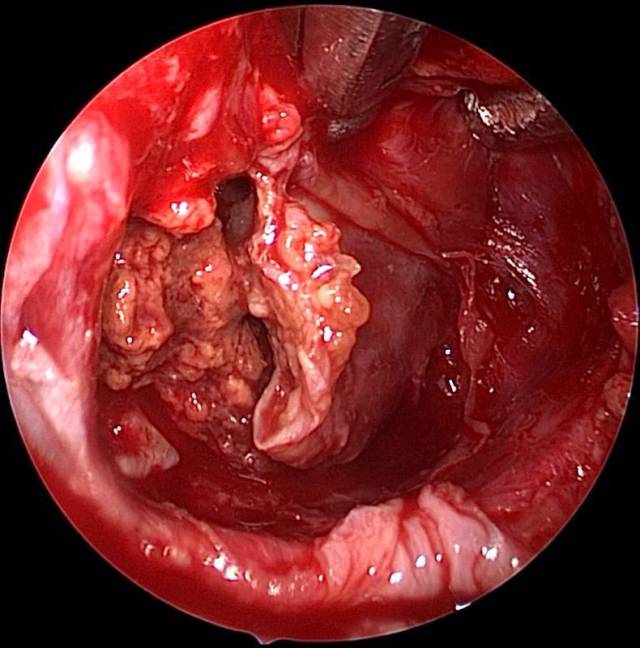

鞍内型颅咽管瘤彻底切除的最佳手术方案-神经内镜下经鼻手术_手机搜狐

图片尺寸640x648